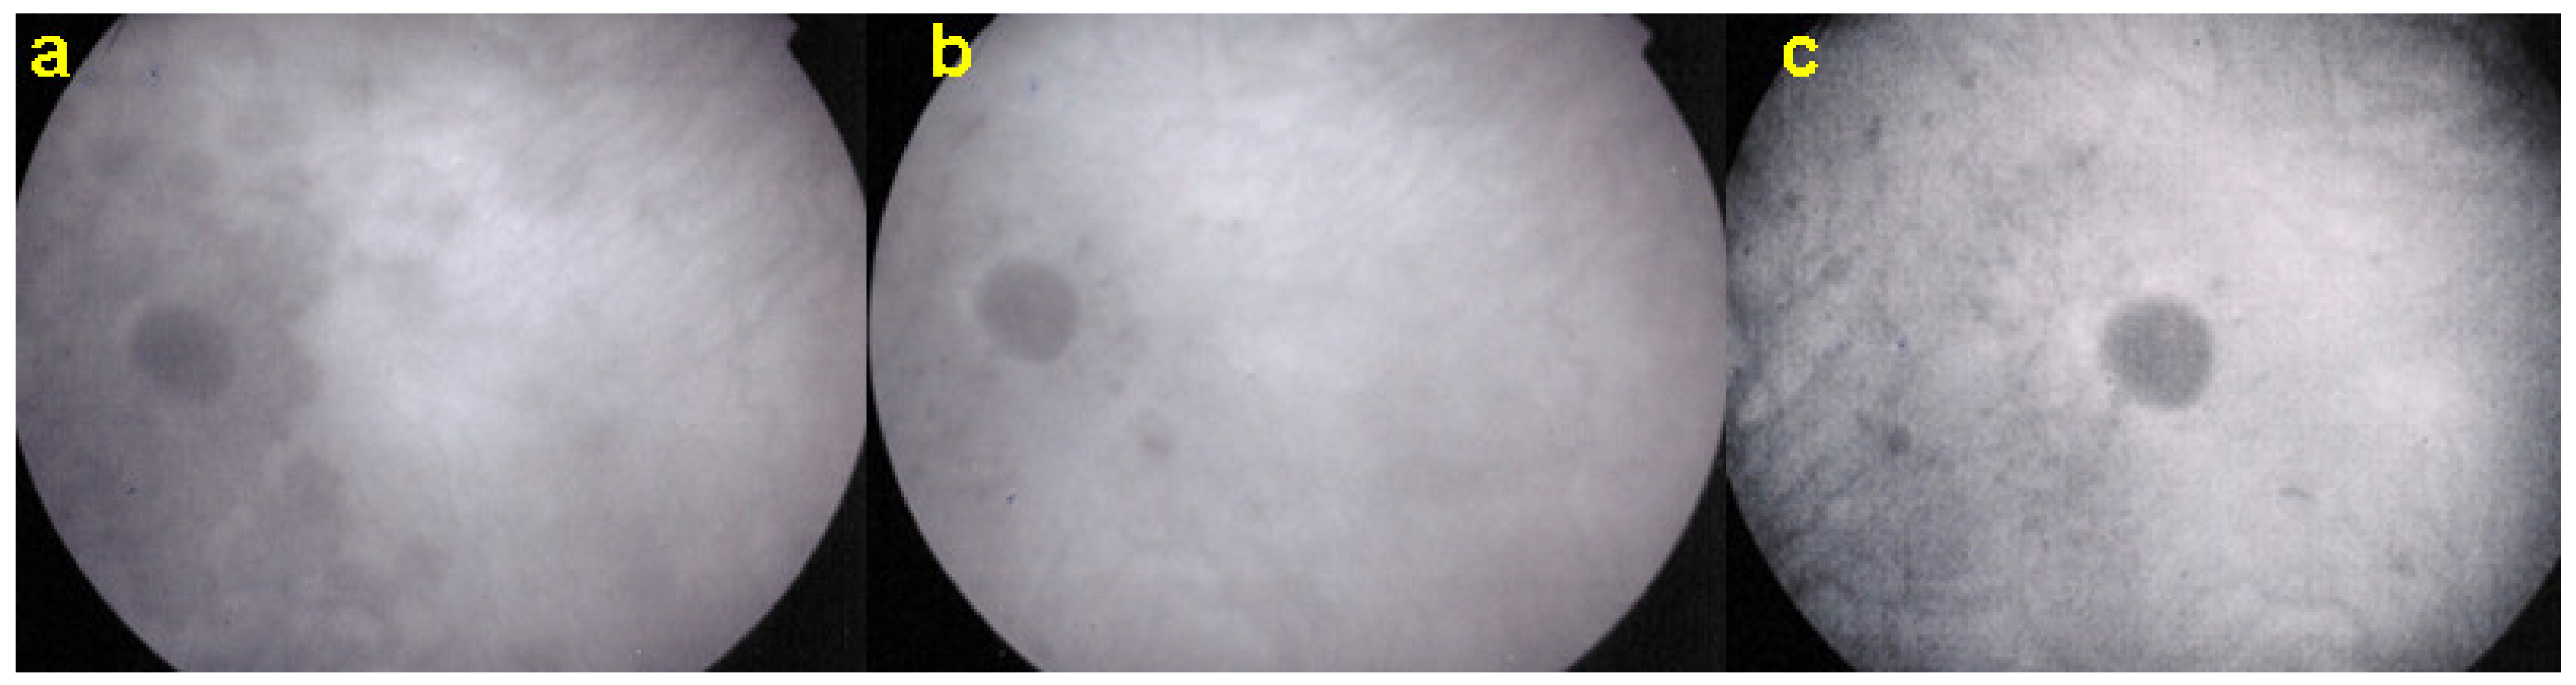

Figure 20.

ICGA pictures of MFC at presentation (a), after 1 month (b) and 4 months (c). Peripapillary confluent hypofluorescence and scattered hypofluorescent areas along superior temporal arcade at presentation (a), which almost completely resolved after one month (b). However, at 4 months, (c) hypofluorescent areas are still seen.

Figure 21.

BAF pictures of MFC at presentation (a), after 1 month (b), and 4 months (c). On the right column of pictures (left eye), hyperautofluorescent areas corresponding to the FA and ICGA lesions can be seen at presentation (a) which, on the (b), have slightly progressed at one month with return to almost normal autofluorescence after 4 months (c). BAF delineates lesions even with more precision than ICGA.